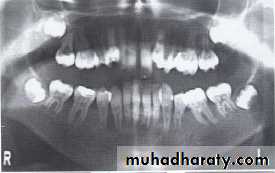

Dentin dysplasia, type I. panoramic & periapical films of the same case show the short and poorly developed roots, obliterated pulp chambers and root canals, and periapical inflammatory lesions.